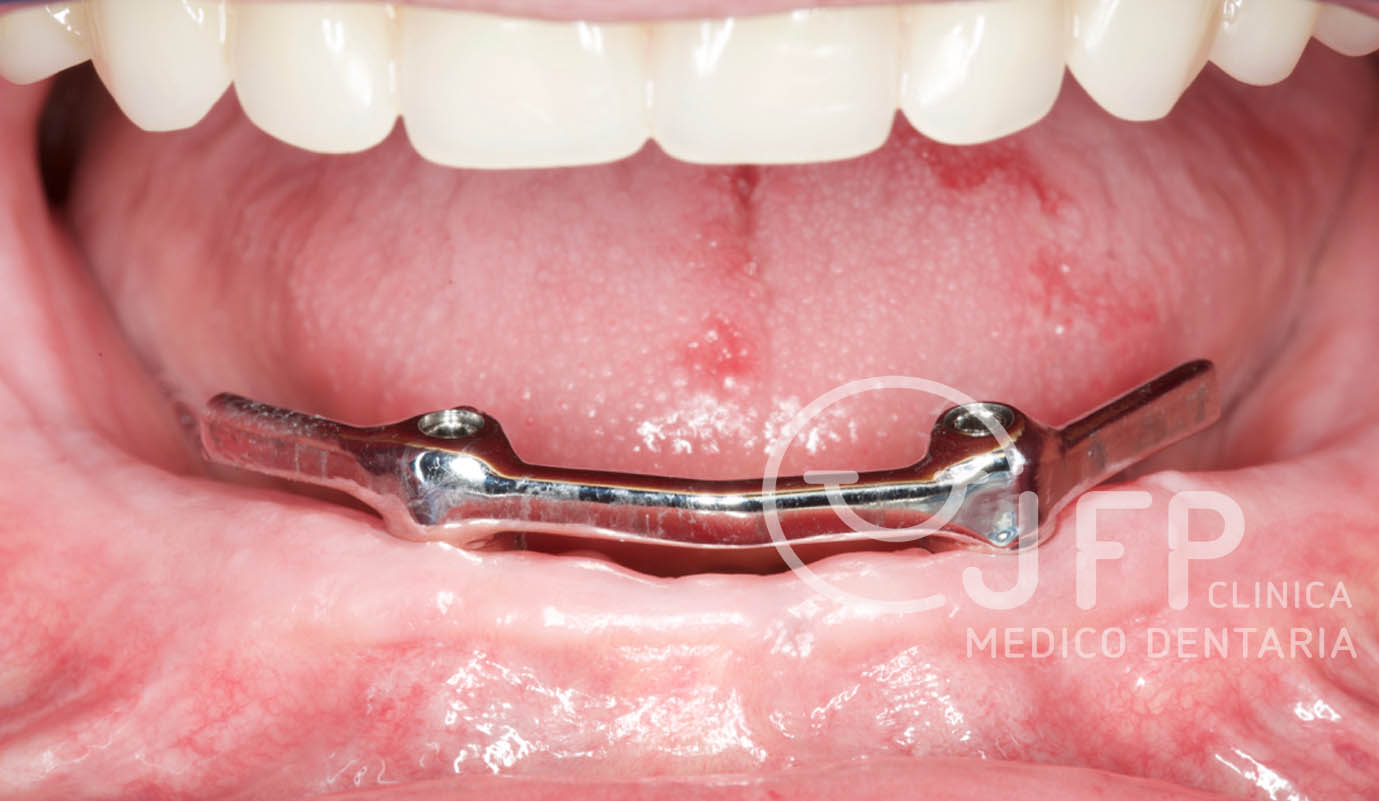

Utilizadas para a substituição de alguns ou de todos os dentes, podem ser ajustadas e apoiadas nas estruturas naturais (gengiva e dentes) ou apoiadas em implantes osteointegrados.

A colocação de implantes revolucionou o tratamento destes pacientes, permitindo a reabilitação com próteses fixas ou removíveis estabilizadas, mas mantendo os princípios clássicos de reabilitação.

Casos de próteses sobre implantes